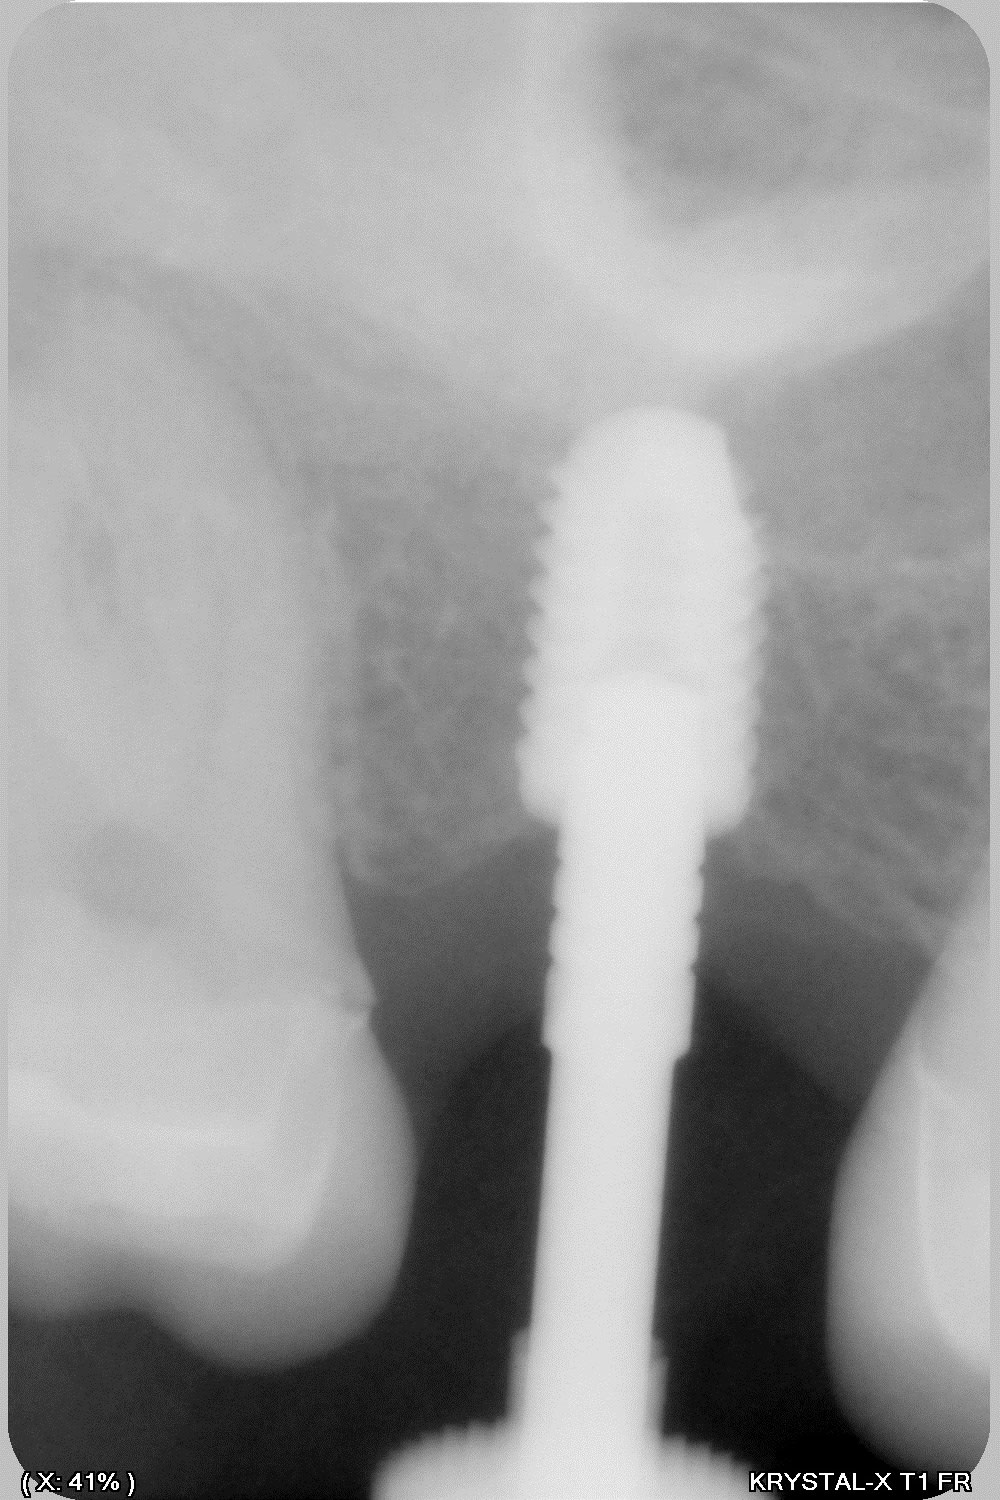

donc tu avais raison Enlaye... le bridge à cassé (sur un carambar quand même:-))

dépose, nettoyage sablage des couronnes récupérable et pose d' implant, uniquement en manuel (os tendre)

ben oui ç était prévisible , à cause des 2 flèches bleues plus haut .

ç est un grand classique ça . quand tu ne peux pas être libre devant , tu t énerves derrière .

et ç est meme pas derriere en fait , mais plutôt dans une zone la plus éloignée possible de devant .

donc ç est derrière et de coté . en diagonale , quoi .

il s avère qu en plus là, derrière , ç est nouveau bridge , donc pas encore usé à sa convenance , tout au moins en latéral .

alors elle s engatse dessus avec beaucoup de force puisque ç est tout pres de l axe charniere .

là où ç est vicieux , ç est que si ton bridge etait pipé avec une grosse erreur occlusale , ben il serait tjs là , entier .

il serait tjs là , pcq si l erreur était plus importante à l arrière ,sur un bridge à la con , elle aurait eu mal soit a l atm soit aux dents antagonistes , et elle aurait cherché un autre endroit pour aller se désénerver . en l occurrence elle t aurait fracassé le bloc ant .

alors maintenant que tu a résolu le pb post ( qui n était qu une conséquence de devant ) méfies , par sympathie pour toi , je te conseillerais de vite vite retoucher au niveau des 2 flèches bleues .